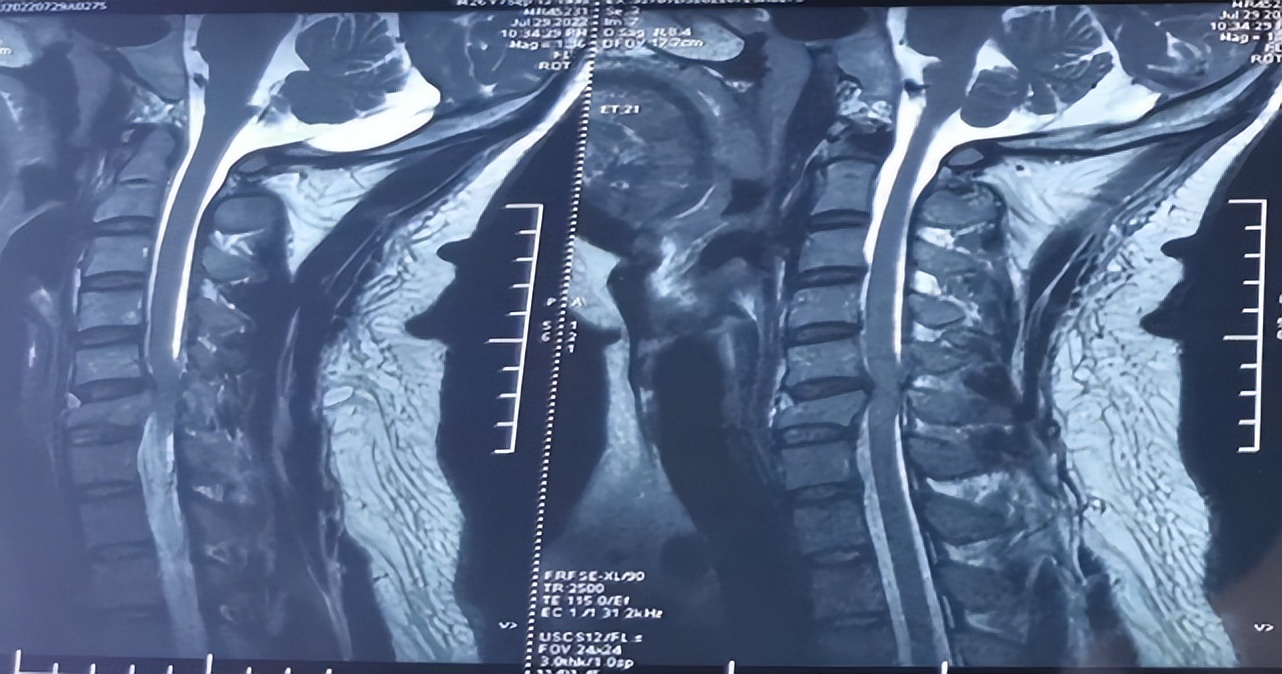

术前检查脊髓损伤平面

收入院后,急诊科医生查体发现,患者意识清楚,头顶部血肿,胸式呼吸消失,腹式呼吸存在,四肢及胸骨角平面以下躯干痛温觉、触觉均减退,会阴区感觉异常;上肢肌力2级,下肢肌力0级,大小便障碍。积极完善头部+颈椎三维CT及颈椎磁共振检查。

急诊科副主任王彦军诊断患者为急性颈椎骨折伴有明显的颈脊髓损伤,需要采取早期手术解除压迫并固定骨折,及时减轻脊髓水肿并恢复更多的神经功能。遂立即启动急诊脊髓损伤绿色通道。术前的全面检查,气道管理,心肺功能评估以及多学科协作会诊,制定详尽周密的诊疗方案,在受伤后18小时,由医院脊柱外科团队急诊行颈椎前路切开复位减压植骨融合内固定术。